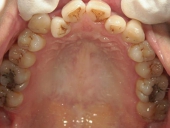

矯正歯科 治療前 下顎

矯正歯科 治療後 下顎